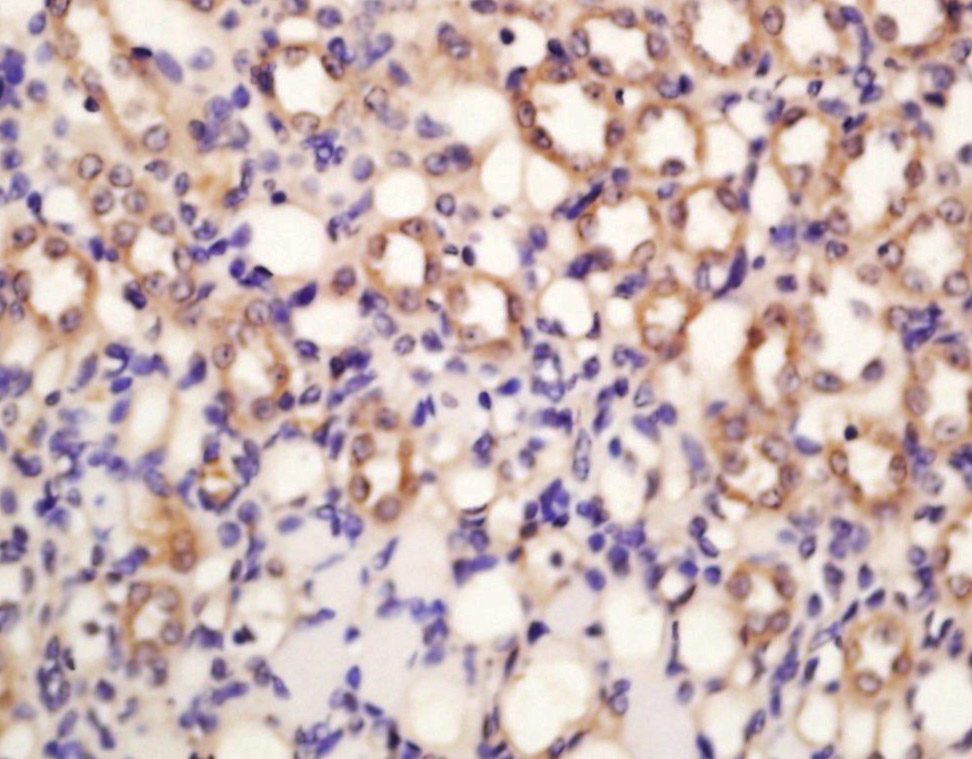

Antigen retrieval: citrate buffer ( 0.01M, pH 6.0 ), Boiling bathing for 15min; Block endogenous peroxidase by 3% Hydrogen peroxide for 30min; Blocking buffer (normal goat serum,C-0005) at 37℃ for 20 min;

Incubation: Anti-SOD1 Polyclonal Antibody, Unconjugated(bs-10216R) 1:200, overnight at 4°C, followed by conjugation to the secondary antibody(SP-0023) and DAB(C-0010) staining